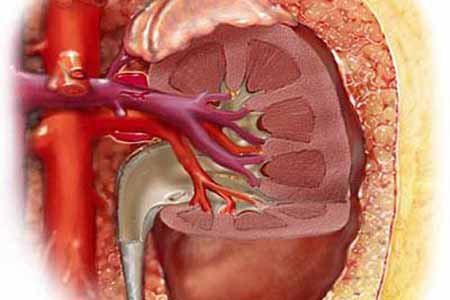

1、引发肾病:类风湿性关节炎患者由于长期服用抗类风湿的药物和非淄体类抗炎药,可能会引起间质性肾炎,虽然进展缓慢,但是会增加肾功能衰竭的机率。